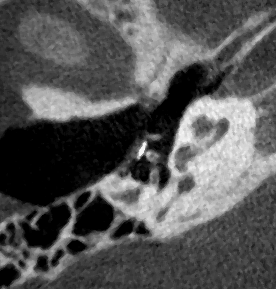

Ambossarrosion mit Stapesprothese Stapesprothese Teflon (Causse) PORP auf Stapes PORP Titan auf Stapes PORP PORP Titan disloziiert Otosklerose Otoskleroseherd TORP Pauke nicht belüftet TORP unter Knorpelinsel disl.